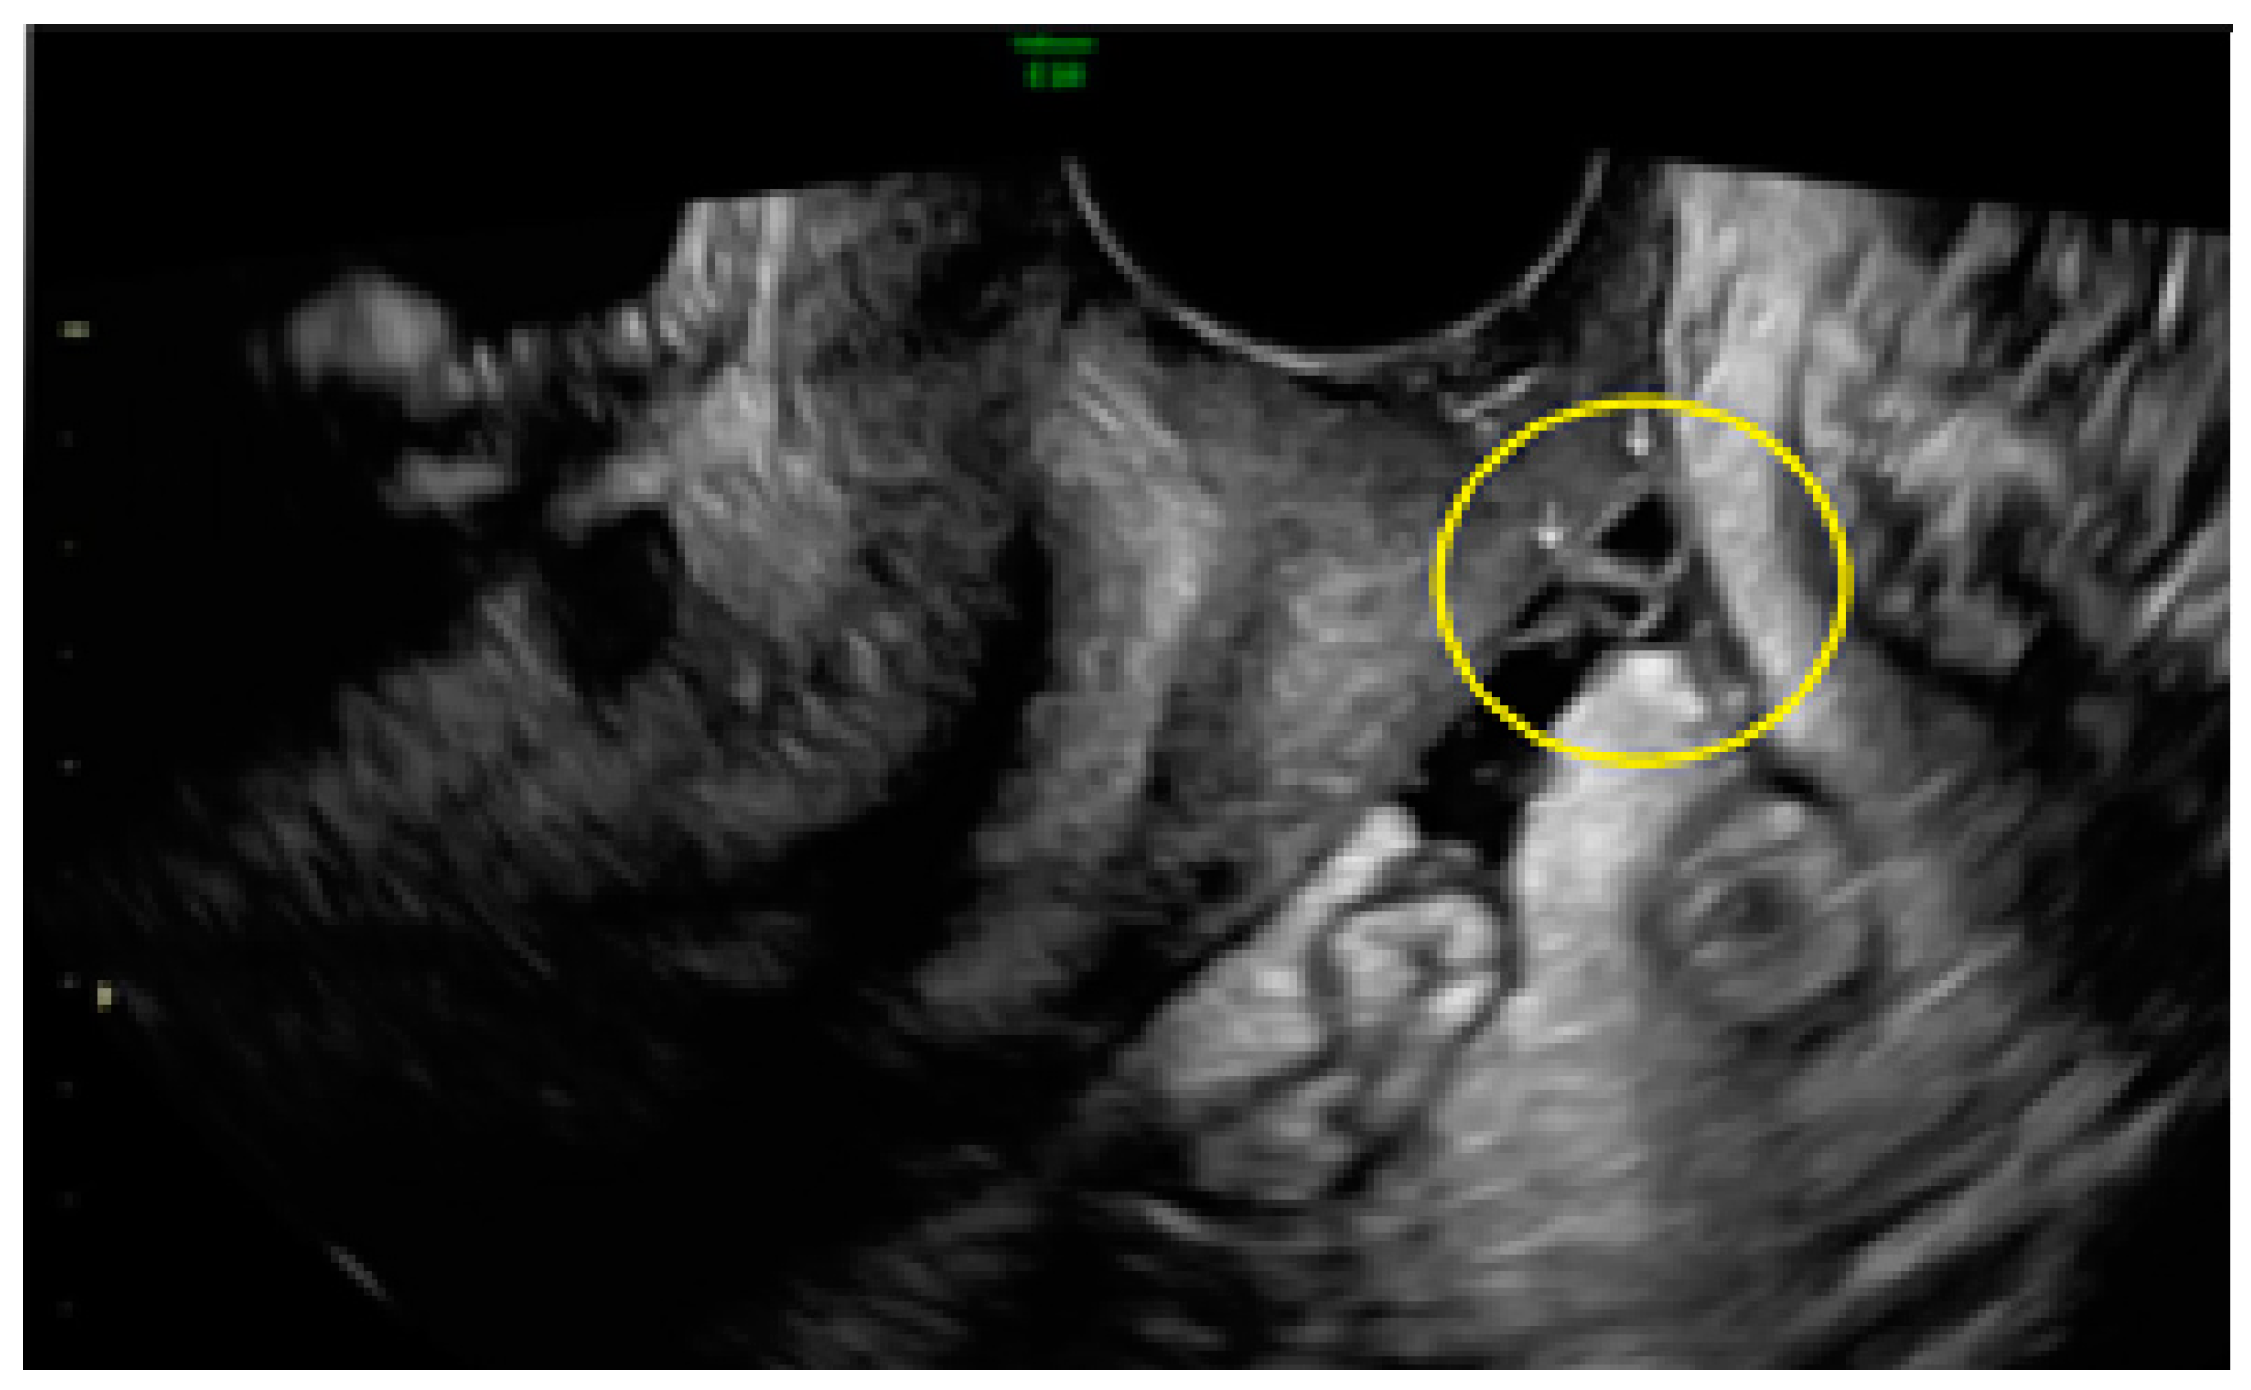

- The lesion may be convex, protruding from the peritoneal surface into the peritoneal cavity (we called this “bulging”), or it may appear as a concave defect in the peritoneum (we called this a “pocket”).